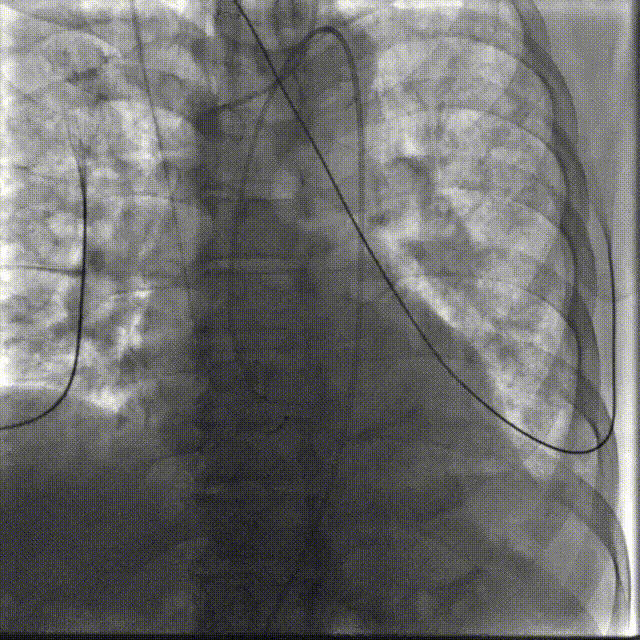

手术过程概览

置入猪尾进行根部造影,造影可见根部钙化不均匀,冠脉灌注良好。

根部造影

20mm球囊预扩,无腰征,冠脉显影良好,无造影剂渗漏。

20mm球囊预扩

TaurusElite AV26瓣膜轻松过弓跨瓣,瓣膜初始定位瓣环0位,120bpm起搏下精准释放,释放到工作位后造影显示锚定充足,位置良好,冠脉未见遮挡,继续完成释放。